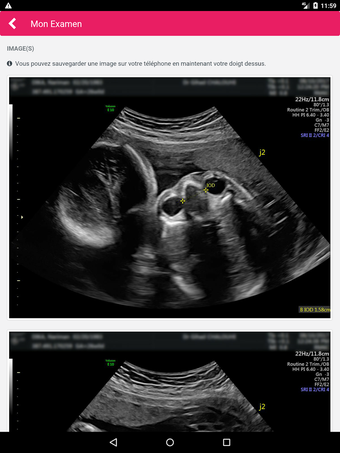

MediFile is an application for medical professionals to manage all of their ultrasound images, reports, and other patient data in one place. The application allows them to scan, view, and save their files directly from their device. The application has the capability to upload reports to the server of the doctor or midwife, for whom the report was sent.

The main advantage of the application is that it makes it very easy for the medical professional to view and share their patient's data with their colleagues. It also facilitates the creation of a patient database and a communication channel for all of the medical professionals working on the same case.